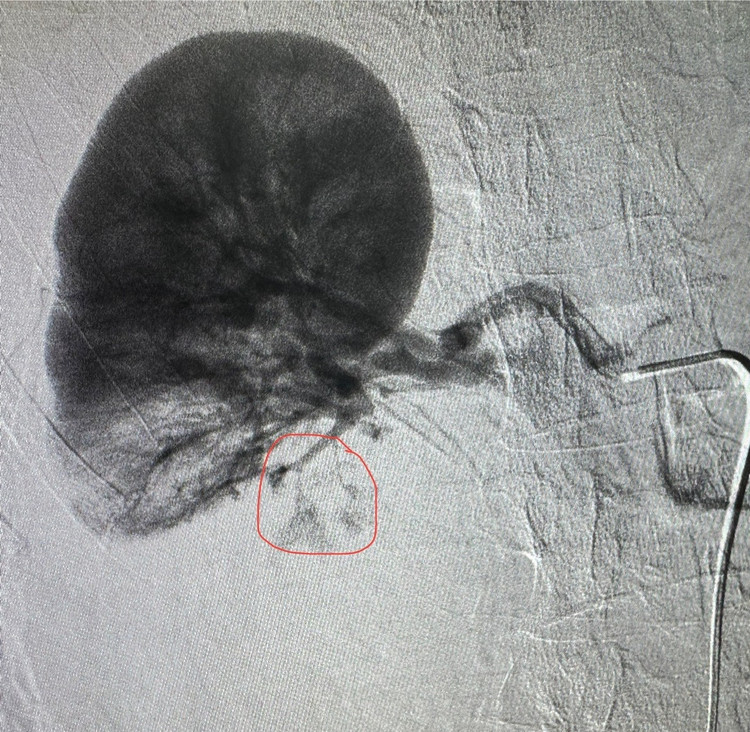

1h sáng ngày 14/7, tại phòng can thiệp – Bệnh viện Đa khoa Hùng Vương, các bác sĩ Khoa Chẩn đoán hình ảnh phối hợp Khoa Hồi sức cấp cứu đã nút mạch cầm máu thành công cho nam bệnh nhân 59 tuổi bị vỡ thận độ IV do tai nạn giao thông nghiêm trọng.

Hình ảnh CT ổ bụng ghi nhận: Vỡ thận phải độ IV; Chảy máu hoạt động; Tụ máu quanh thận. Đồng thời, bệnh nhân còn vỡ xương sọ và xương mặt.

Sau hội chẩn liên khoa bệnh nhân được tiên lượng rất nặng. Thay vì phải chuyển tuyến – tiềm ẩn nhiều rủi ro như sốc mất máu, ngừng tuần hoàn trên đường đi, bệnh nhân đã được xử trí kịp thời ngay tại tuyến cơ sở.

Trong tình huống nguy kịch, bệnh nhân đã được can thiệp nút mạch ngay trong đêm tại Bệnh viện Hùng Vương. Nhờ xử trí kịp thời, các bác sĩ đã kiểm soát chảy máu, bảo tồn tối đa nhu mô thận và giành lại sự sống cho người bệnh. Hiện bệnh nhân đang tiếp tục được theo dõi sát tại Khoa Hồi sức cấp cứu.